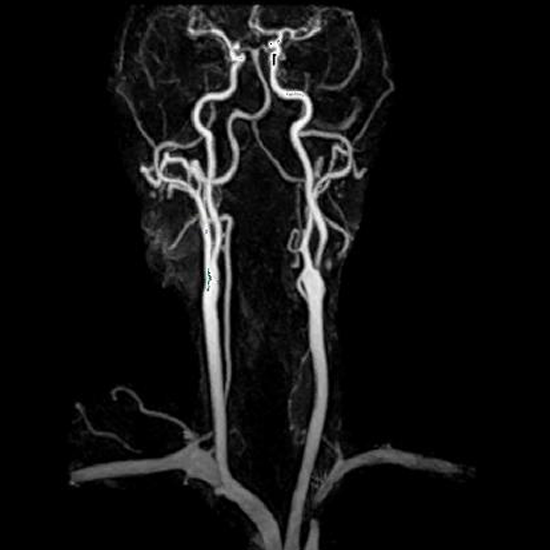

MR Angiography of the Neck with Contrast allows for visualizing the neck's blood arteries. It uses contrast agents to improve photographs.

MR Angiography Neck with Contrast is a Magnetic Resonance Imaging non-invasive medical diagnostic tool used to diagnose the blood vessels of the neck with contrast. MR Angiography Neck with Contrast is used to show abnormalities in the blood capillaries of the neck.